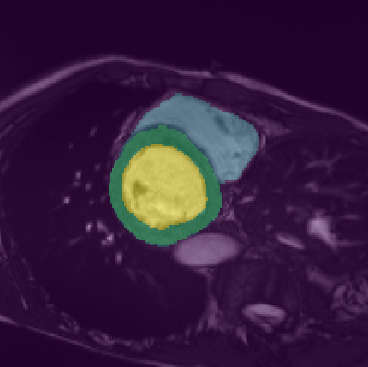

In this paper, we aim to improve the performance of semantic image segmentation in a semi-supervised setting in which training is effectuated with a reduced set of annotated images and additional non-annotated images. We present a method based on an ensemble of deep segmentation models. Each model is trained on a subset of the annotated data, and uses the non-annotated images to exchange information with the other models, similar to co-training. Even if each model learns on the same non-annotated images, diversity is preserved with the use of adversarial samples. Our results show that this ability to simultaneously train models, which exchange knowledge while preserving diversity, leads to state-of-the-art results on two challenging medical image datasets.